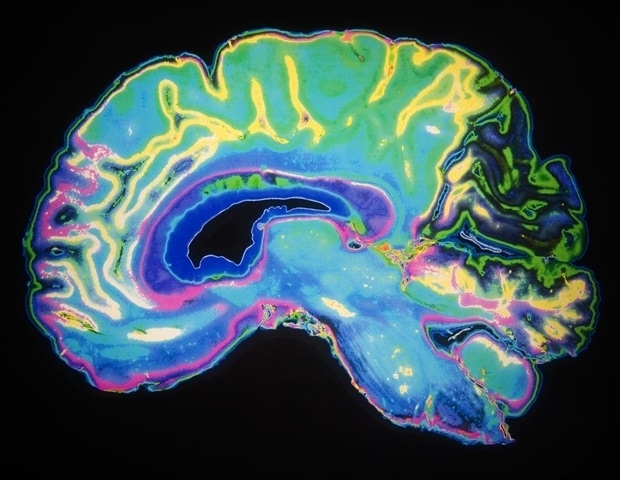

Исследователи из Университета штата Вашингтон обнаружили, как нервная цепь – или связь между двумя областями мозга – вызывает рецидив после употребления опиоидов. Это открытие может привести к более эффективному лечению расстройств, связанных с употреблением опиоидов.

В исследовании, опубликованном в Journal of Neuroscience, исследователи из кафедры интегративной физиологии и нейронаук Колледжа ветеринарной медицины WSU использовали доклиническую модель, чтобы смоделировали употребление опиоидов у людей и обнаружили, что снижение активности в определенной нейронной цепи, связывающей прелимбическую кору и паравентрикулярный таламус, значительно снижает поведение, связанное с поиском наркотиков. Проект возглавила аспирант Эллисон Дженсен, первый автор исследования, работавшая под руководством доцента Джузеппе Джаннотти.

Известно, что паравентрикулярный таламус играет центральную роль в обработке сигналов, связанных с наркотиками, и мотивационных состояний, но, что важно, исследователи WSU обнаружили, что сигналы прелимбической коры играют важную роль в активации паравентрикулярной коры. Когда команда снизила активность этого мозгового пути, поведение, связанное с поиском героина, значительно снизилось.